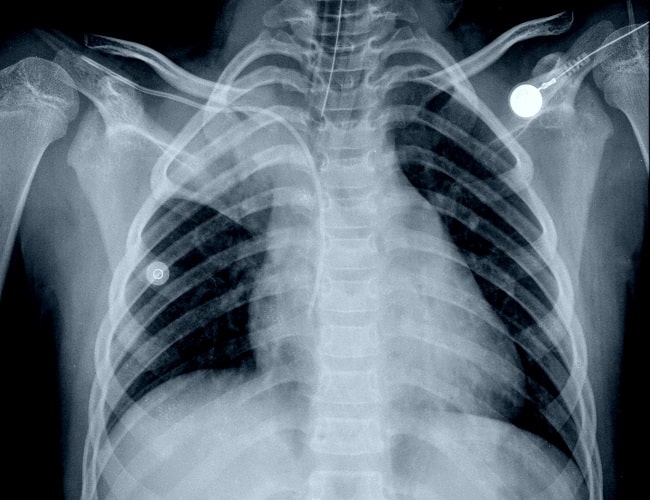

Gambar 1. Atelektasis pada Rontgen Thorax. Sumber: Shutterstock, 2022.